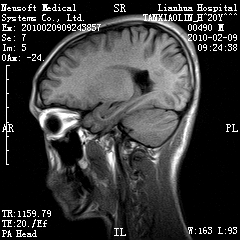

20岁男性患者,平时偶有头痛而无其他不适,现因持续头痛服药后无缓解而来院就诊。

松果体囊肿?

松果体区占位继发轻度脑积水?该患者有ct资料,我已发上。

考虑松果体囊肿。